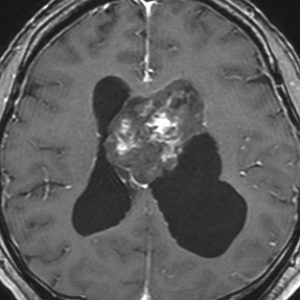

巨大な上衣下腫,でも良性のもの

52歳の男性で,2008年に脳ドックで見つかって無症状でした。中枢性神経細胞種 central neurocytomaを疑いましたが,上衣下腫 subependymomaはまったく考慮に入れませんでした。壮年男性でしたから経過観察しました。右側は2019年,11年後のものです。徐々に増大して水頭症になり歩行障害がでてきました。

手術前の画像です。血管が豊富で大きな導出静脈がみられ,腫瘍内出血もあります。ガドリニウムでは部分的に増強されます。CISS/FIESTAの画像では,透明中核から発生したようにみえて,脳浸潤は全くありません。脳弓は腫瘍の底面にありますが,もちろん境界はっきりしません。これらもcentral neurocytomaの画像所見として捉えられるものです。

transcallosal approach 経脳梁法で亜然摘出しました。底面には脳弓があって剥離できないから全摘出はできません。病理所見は,のう胞形成を伴う線維性基質の中に楕円形の細胞が索状または小巣状に増生するものでsubependymomaと診断されました。異型は軽度で,核分裂像はなく,MIB-1染色率は1%以下のWHO grade Iの所見。EMAは細胞質にdot likeに陽性でしたがわずかであり,ependymomaとの合併腫瘍の診断には至りませんでした。